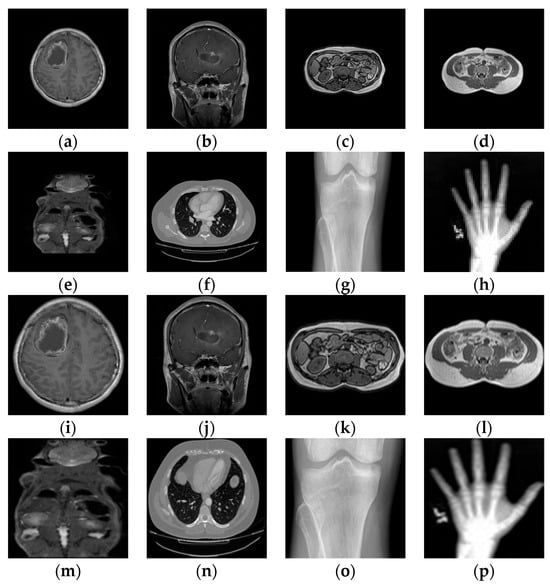

In this part, Python 3.6 is used to simulate the proposed scheme and evaluate its performance. The medical image set was chosen for experimental testing to provide a better estimation of the algorithm’s performance. As shown in Figure 7, eight medical images of different sizes, different body parts, and different types were selected for simulations to verify the effectiveness of the scheme.

Figure 7.

The standard medical images used for testing. (a) Brain 01 MRI (512 × 512); (b) Brain 02 MRI (512 × 512); (c) Pulmonary 01 CT (256 × 256); (d) Pulmonary 02 DICOM (256 × 256); (e) Pancreas MRI (180 × 180); (f) Chest CT (256 × 256); (g) Knee X-ray (300 × 162); (h) Hand X-ray (64 × 64); (i–p) The ROS region of extracted. (i) Brain 01 (352 × 352); (j) Brain 02 (464 × 464); (k) Pulmonary 01 (176 × 176); (l) Pulmonary 02 (176 × 176); (m) Pancreas (120 × 120); (n) Chest (228 × 188); (o) Knee (212 × 162); (p) Hand X-ray (46 × 60).